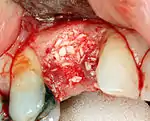

An incision is made across the area and the flap of gingiva is opened to show the bone of the jaw.

An incision is made across the gingiva, and the flap of tissue is reflected to show the bone of the jaw.

If bone width is inadequate it can be regrown using either artificial or cadaveric bone pieces to act as a scaffold for natural bone to grow around.

For an implant to osseointegrate, it needs to be surrounded by a healthy quantity of bone. In order for it to survive long-term, it needs to have a thick healthy soft tissue (gingiva) envelope around it. It is common for either the bone or soft tissue to be so deficient that the surgeon needs to reconstruct it either before or during implant placement.[32]:1084

Hard tissue (bone) reconstruction

To achieve an adequate width and height of bone, various bone grafting techniques have been developed. The most frequently used is called guided bone graft augmentation where a defect is filled with either natural (harvested or autograft) bone or allograft (donor bone or synthetic bone substitute), covered with a semi-permeable membrane and allowed to heal. During the healing phase, natural bone replaces the graft forming a new bony base for the implant.[38]:223